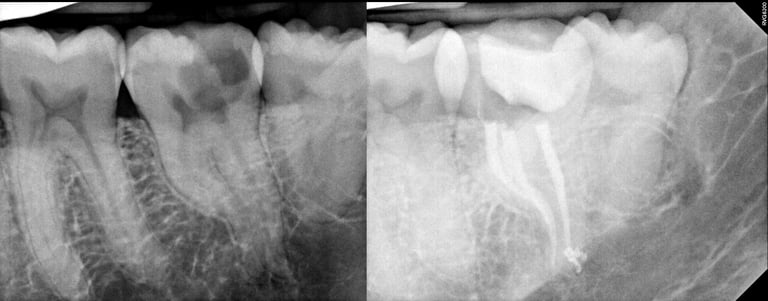

Gallery 2: Retreatment Cases

Retreatment Root Canal Cases with preoperative and postoperative radiographs.

#30 ReTx (original RCT had missed canal)